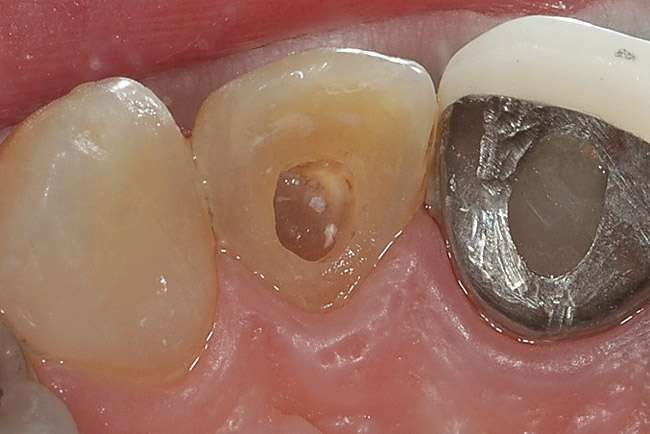

Figure 12  The initial examination and radiograph determined that the dark lateral incisor was abscessed. After endodontic therapy, the tooth was then ready for bleaching. Had bleaching been performed without the radiograph, the abscess would have remained untreated and further damaged the tooth.

Figure 12

Figure 13   The endodontic access opening should be enlarged until it can be certain that all the remaining brown pulp tissue has been removed from the lateral walls of the pulp chamber as well as the incisal extent. Pulps that became necrotic when the tooth was young often have pulp chambers much larger than the endodontic access opening.

Figure 13

Figure 14  Even before bleaching the tooth, the removal of the brown necrotic pulp remnants and dental materials makes the tooth much lighter. This occurrence demonstrates how the materials inside the tooth affect the color of the outside.

Figure 14

When performing internal bleaching on a non-vital tooth that has received endodontic therapy, it is important to clean out the inside of the pulp chamber (Figure 12). Often, when endodontic therapy is performed because of trauma, the pulp chamber is large, with high pulp horns. The access opening to the apex may not include debridement of the chamber (Figure 13). The restorative dentist should open the access opening enough to access both the incisal extent as well as the lateral extent of the pulp chamber. Often, removal of the remaining pulp chamber will significantly alter the color of the tooth, even before the bleaching has begun (Figure 14).